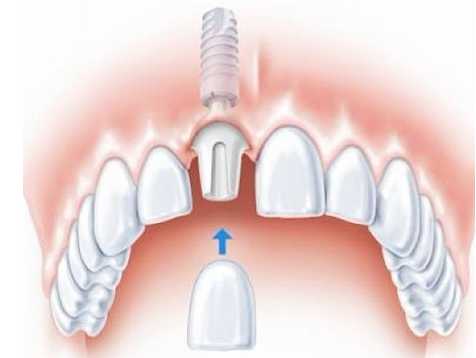

維港口腔種植牙醫生表示,其實種牙手術系微創牙槽外科手術,呢個手術並冇大家想像嘅咁恐怖。牙齒種植全過程種會採用局部麻醉,手術感覺類似掹牙,創傷小,幾乎冇乜痛苦,所以大家無需過度擔心疼痛嘅問題。

2、出血少、創傷小,種牙更舒適

依家嘅種植技術可利用微小切口將人工牙根「種」入口腔內,擺脫傳統種植牙切開翻起牙肉、縫合、拆線等步驟,將創傷降低到非常小程度,大大減少咗腫痛和出血量,大幅度縮短咗種植過程所需嘅時間,而且減少咗感染嘅風險。